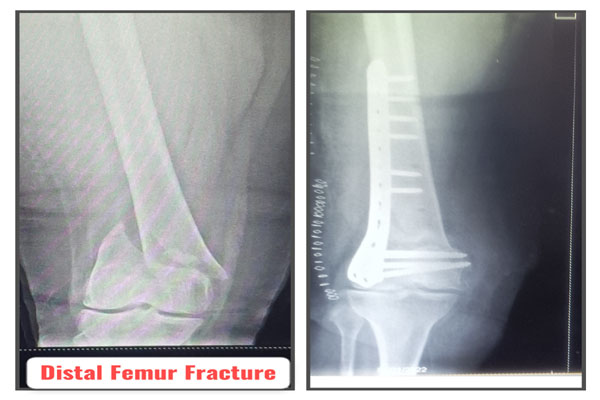

Fracture of bones is commonly handled by almost all orthopaedic surgeons in India. But dealing with comminuted intra-articular fractures (involving joints) is a night mare for most of them. It requires special expertise and experience to deal with such kind fractures. It can involve pelvic acetabular fracture, upper portion of thigh bone ( hip), lower portion of thigh bone ( femur), upper portion of arm bone (humerus head), lower portion of arm bone (humerus), lower portion of forarm bone (lower end of radius) fracture of heel bone, etc. The idea is to maintain the joint (articular) integrity and prevent the permanent loss of movements at that joint. It requires image intensifier (c-arm) to do these surgeries. May be artificial bone or autograft (patient’s own bone taken from iliac bone) to fill in the bone defect/ loss if present. The fracture may take 2- 3 months to heal. Patient may require prolonged physiotherapy to gain near normal range of motion exercises.